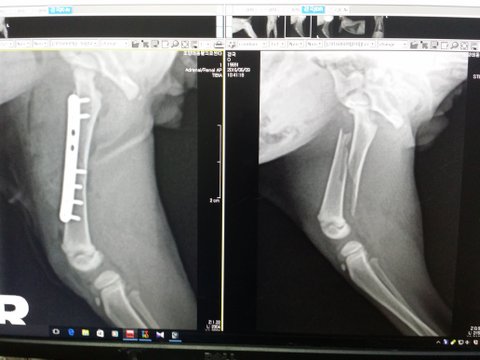

저는 6월초 불의의 자전거 사고로 다리를 다쳤습니다~몇일이 지났는지 모르겠지만 도로가 풀속에 숨어있다 이러다 죽겠다싶어 몇걸음 때는 순간 너무이쁜 실제나이는 서른후반노처녀 이지만 20대같은 이쁜이모의 도움으로 병원가서 사진도찍고 주사도맞고 다리 수술도했습니다~

뼈는 자~알 붙었답니다~ 그런데 성장판이 살짝 어긋나있다고하네요...의사샘이 제가 아직 많이 어려서 어떻게 될지는 모르겠다 그러시네요~ 헐~

6월6일 김해 경찰서 맞은편 공사장앞에서 절 발견했고, 수술한지 2주 넘었고, 앞으로 다리때문에는 병원갈일 없습니다~태어난지는 2개월 조금 넘었습니다~